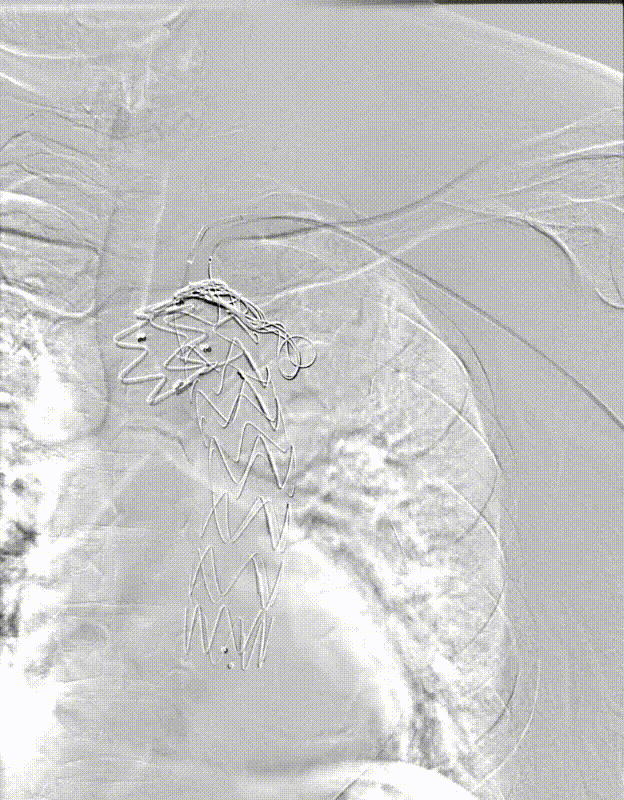

【病例2】主动脉B型夹层,

2016年外院TEVAR术后II型内漏

术后8年随访发现假腔明显扩大,最大直径达96mm,伴胸背疼痛,有手术干预指征。

再干预方案:弹簧圈栓塞分支血管(LSA栓塞),覆膜支架+封堵器+弹簧圈覆盖左肾动脉破口。

修复结果:进入假腔血流明显减少,胸背疼痛症状明显缓解。

二次手术前CTA

LSA弹簧圈栓塞

造影内漏消失